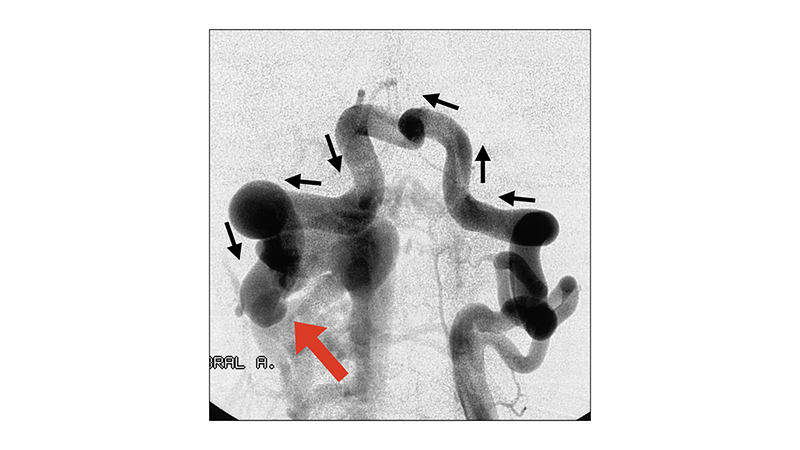

- Εκλεκτική αγγειογραφία της αριστερής σπονδυλικής αρτηρίας σε προσθιοπίσθια λήψη. Παρατηρείται πλήρης υποκλοπή από την βασική αρτηρία που δεν σκιαγραφείται, με αναστροφή της ροής στην δεξιά σπονδυλική αρτηρία (μαύρα βέλη) μέχρι του σημείου της σπονδυλο-σπονδυλικής επικοινωνίας στο ύψος του Α2 διαστήματος (κόκκινο βέλος).